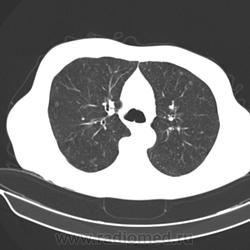

Здравствуйте! Пациент 1951 г. поступил в неврологическое отделение по поводу пареза нижней конечности, жалобы на боли в поясничном отделе позвоночника. Выполнили КТ пояснично-кресцового отдела: кт-картина остеобластических mts в телах позвонков L1-L3, крыле подвздошной кости слева. Клиницисты стали искать первичный очаг. Выполнили КТ органов грудной клетки. По всем легочным полям кольцевидные образования (очаги?) - аспергилёз? Прошу коллег помочь разобраться с заключением.

кистозный паттерн, неравномерно утолщенные стенки, распределение преимущественно периферическое, больше в верхних отделах.

по первому впечатлению - лангергансоклеточный гистиоцитоз (правда возраст не подходит, он чаще у молодых бывает), может сочетаться с раком. Надо копать дальше.

и вообще может быть несколько патологий в одном человеке: cr простаты/моч пузыря с бластическими мтс в позвонки и таз с наличиями в них участков распада и гистиоцитоз (который вероятно тянется с давних времен).

у меня пока связать изменения легких и такие мтс в позвонки с очагом в печени воедино не выходит. похоже разные тут патологии сидят.

Я про легкие и говорил, но больше склоняюсь к кистозным метастазам.

Small Cavitary Lung Lesions

1.Septic emboli

2.Rheumatoid nodules

3.Squamous or transitional cell mets

4.Wegener’s Granulomatosis